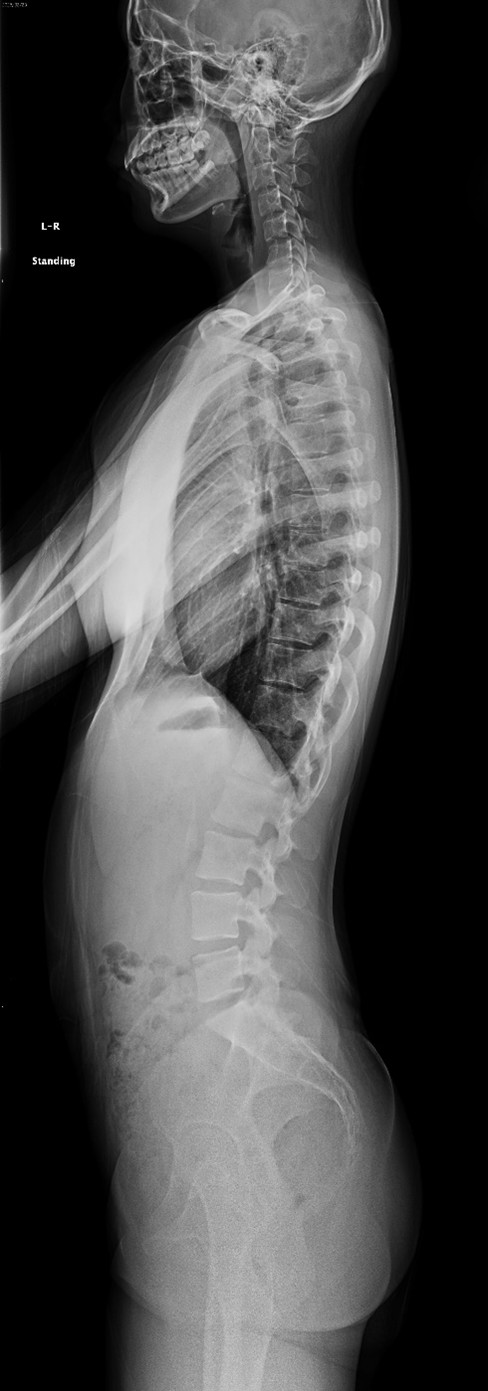

一般撮影装置

当院では一般撮影装置を2台使用しています。脊椎、膝関節、股関節など全身の骨を撮影しています。1日の検査数が一番多いです。

骨密度測定

骨密度が高いほど、骨は強く、骨折のリスクが低くなります。

主に測定する部位は腰椎、大腿骨頸部(太ももの付け根)です。

腰椎と大腿骨で測定する理由は

・測定誤差が少なく正確に検査できるから

・骨折を起こしやすい部位である

検査結果を患者様にも渡しているのでご自身でも確認していただけます。